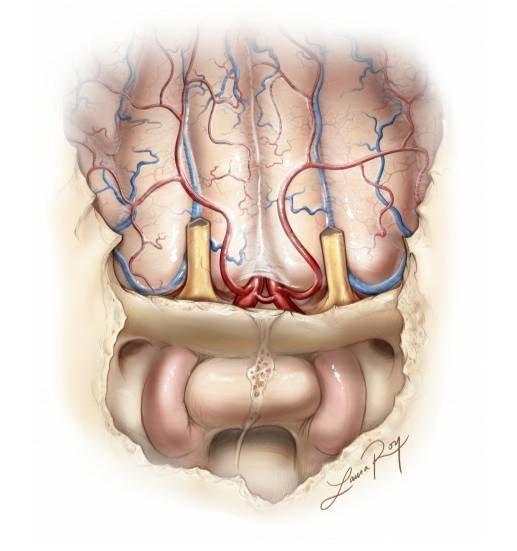

图3. 嗅沟以及嗅沟与周围结构的解剖关系上面观。注意在轴位沿颅底中线解剖时眶顶的变化。在沿颅底阻断肿瘤血供时,应该记住这些解剖关系。术中主要出血来源于筛前及筛后动脉,经鼻内镜入路,在早期控制肿瘤基底这两组动脉,可以提高手术效率(图片来自AL Rhoton,Jr)。

图4:通过经鼻内镜观察到的嗅沟脑膜瘤的血管解剖,注意筛前和晒后动脉的位置(图片来自AL Rhoton,Jr)。下排图片显示了最终骨性暴露。